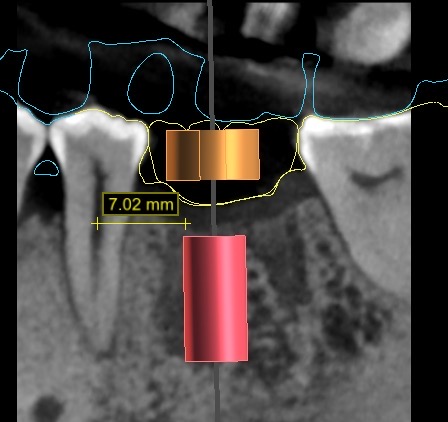

再來,透過電腦程式搭配 3D斷層掃描CT 的應用,可以準確地測量出齒槽骨立體的寬度與深度,以便找出最適當的植牙位置與角度。這些資訊也可判斷出植牙位置的骨頭條件是否足夠?如果需要補骨手術時,需要用何種的手術方式重建? 讓我們在手術之前就可以有一個精準的規劃。

依照電腦的規劃結果,可製做出需要的手術導引版和相關的植牙零件,使得手術結果與電腦模擬達到零誤差。